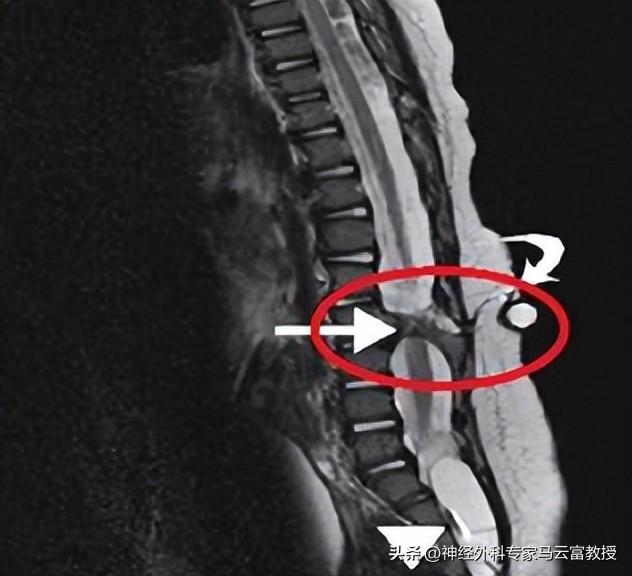

醫生通常會藉助X光、CT或核磁共振(MRI)等影像檢查來明確診斷。

MRI顯示脊柱裂